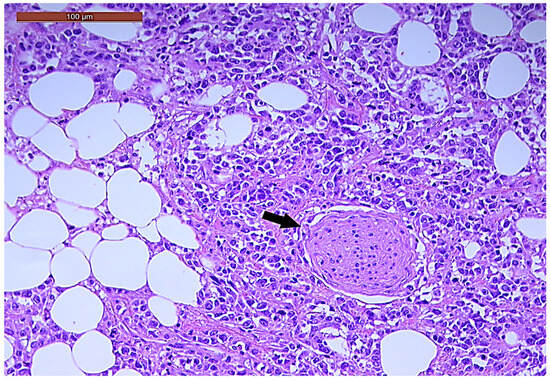

LVI was detected in 31 cases (51.7%), and perineural invasion (PnI) was identified in 20 cases (33.3%) (Figure 1 and Figure 2). EMVI and IMVI were registered in 31 (51.7%) and 21 cases (35%), respectively. Regarding Bd and PDC categories, a significant proportion of tumors were recorded as Bd1, while Bd2 was less common (49 cases; 81.6% vs. 7 cases; 11.7%) (Figure 3); moreover, a large proportion were classed as the PDC1 grade (Figure 4), while the PDC2 grade was less common (55 cases; 91.7% vs. 4 cases; 6.7%). The main clinicopathological characteristics of the study group are summarized in Table 4.

Figure 2. Perineural invasion (arrow) in a ypT3-stage LARC case (H&E staining, 200×).